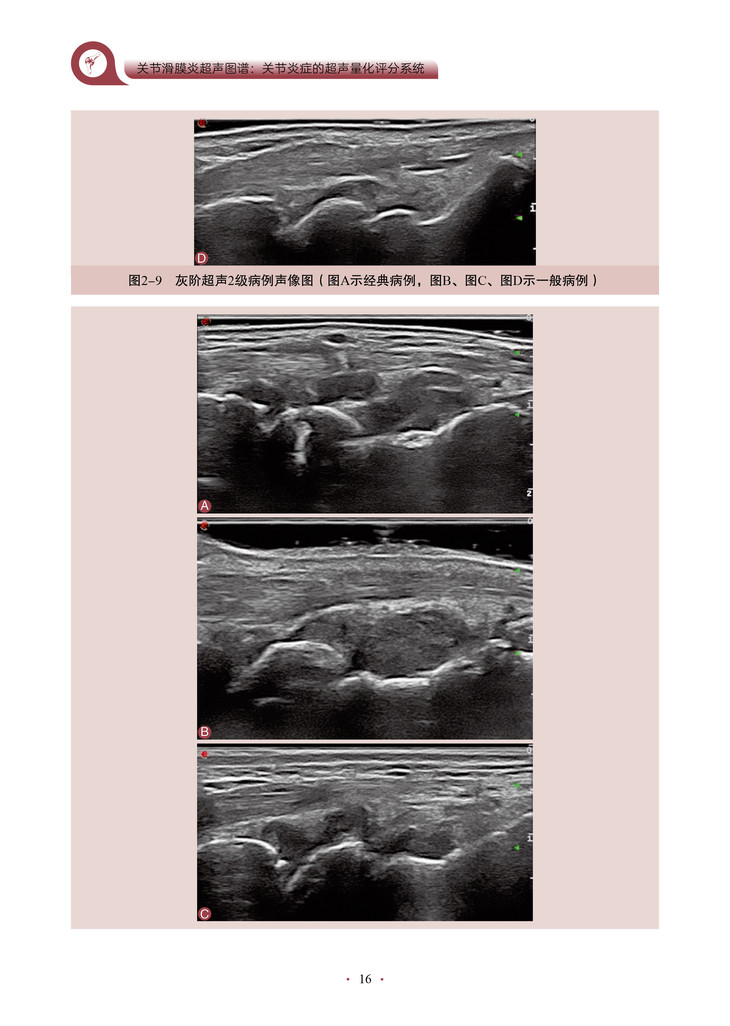

书名:关节滑膜炎超声图谱:关节炎症的超声量化评分系统

本书的核心内容是将超声技术应用于关节炎程度的评估,特别是对关节滑膜炎症的评分和客观量化。通过详细地介绍超声评分系统的构建和应用,作者为我们展示了一种全新的、基于客观指标的关节炎评估方法。该书深入探讨了关节滑膜超声图像的解读和分析,教导读者如何识别和评估关节炎引起的滑膜病变。通过使用可靠的超声评分系统,医师和研究人员能够更准确地量化关节炎患者的炎症程度和疾病进展,从而更好地指导治疗和监测疗效。